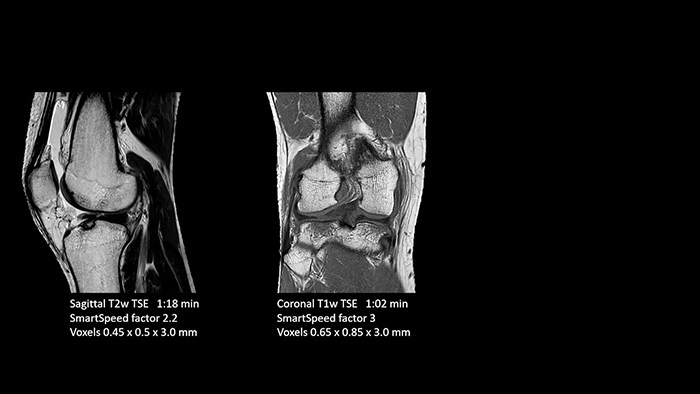

Dr. Schröter says their MSK images show high contrast and extremely high quality. He mentions the menisci as an example. “We use a 3D proton density weighted fatsat sequence, thickness is 0.3 mm and scan time 3 minutes. The MPRs show an unbelievable resolution. Very small tears and even fraying of the tip of the meniscus become visible, which is normally only possible in arthroscopic surgery.

When imaging the small joints of the fingers and the thumb we achieve extraordinary quality. Using SmartSpeed we succeed in displaying even very small structures anatomically correct, enabling us to see the extent of possible injuries. Tendons and ligaments appear with higher resolution so we can better see the injury pattern and describe and delimit it.

With these 3D scans we can create freely selectable MPRs that are pin-sharp, allowing us to easily see pathological changes.”